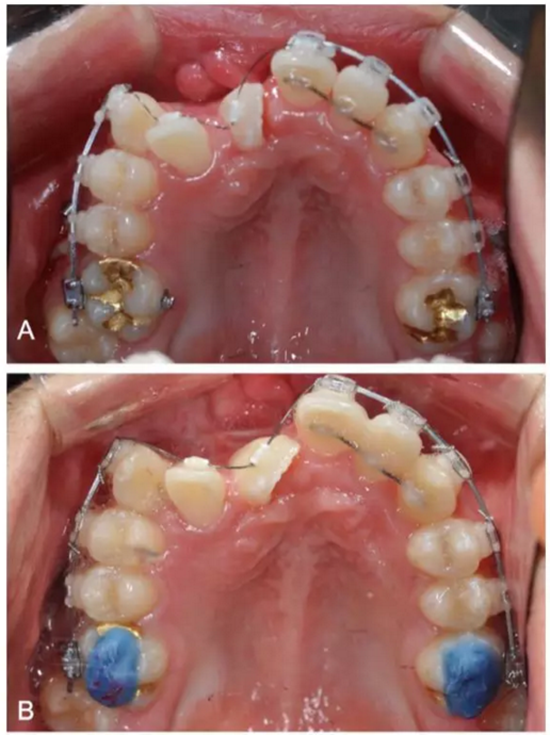

弓絲換至0.019*0.025-inch不銹鋼絲時,開始進行外科手術暴露阻生牙。由于易位情況嚴重,三維向阻擋嚴重,因此需要行兩期手術。

一期手術主要是牽引側切牙和尖牙:于上頜前牙區(qū)唇側作切口,翻全厚瓣;腭側面較??;在尖牙唇側、側切牙腭側粘扣掛結扎絲牽引,通過一輔助鈦板及樹脂等連接至弓絲上;采用閉合式導萌技術,將皮瓣復位縫合,僅結扎絲穿過粘膜;2周內(nèi)軟組織得以愈合,牽引開始。先通過正畸力,近中移動側切牙,遠中移動尖牙。10個月后,阻生牙牙冠萌出,側切牙、尖牙的易位得以矯正。

二期手術主要是牽引中切牙:于上頜前牙區(qū)腭側作切口,翻全厚瓣,在切牙唇側粘扣掛結扎絲牽引;軟組織愈合后,牽引開始。為施加合適的垂直向力,在下頜前牙區(qū)放置C型管,掛橡皮筋牽引。14個月后,切牙牙冠萌出。使用mini管代替托槽,對切牙、尖牙進行矯治;矯治過程采用輕力,0.014-in鎳鈦絲。